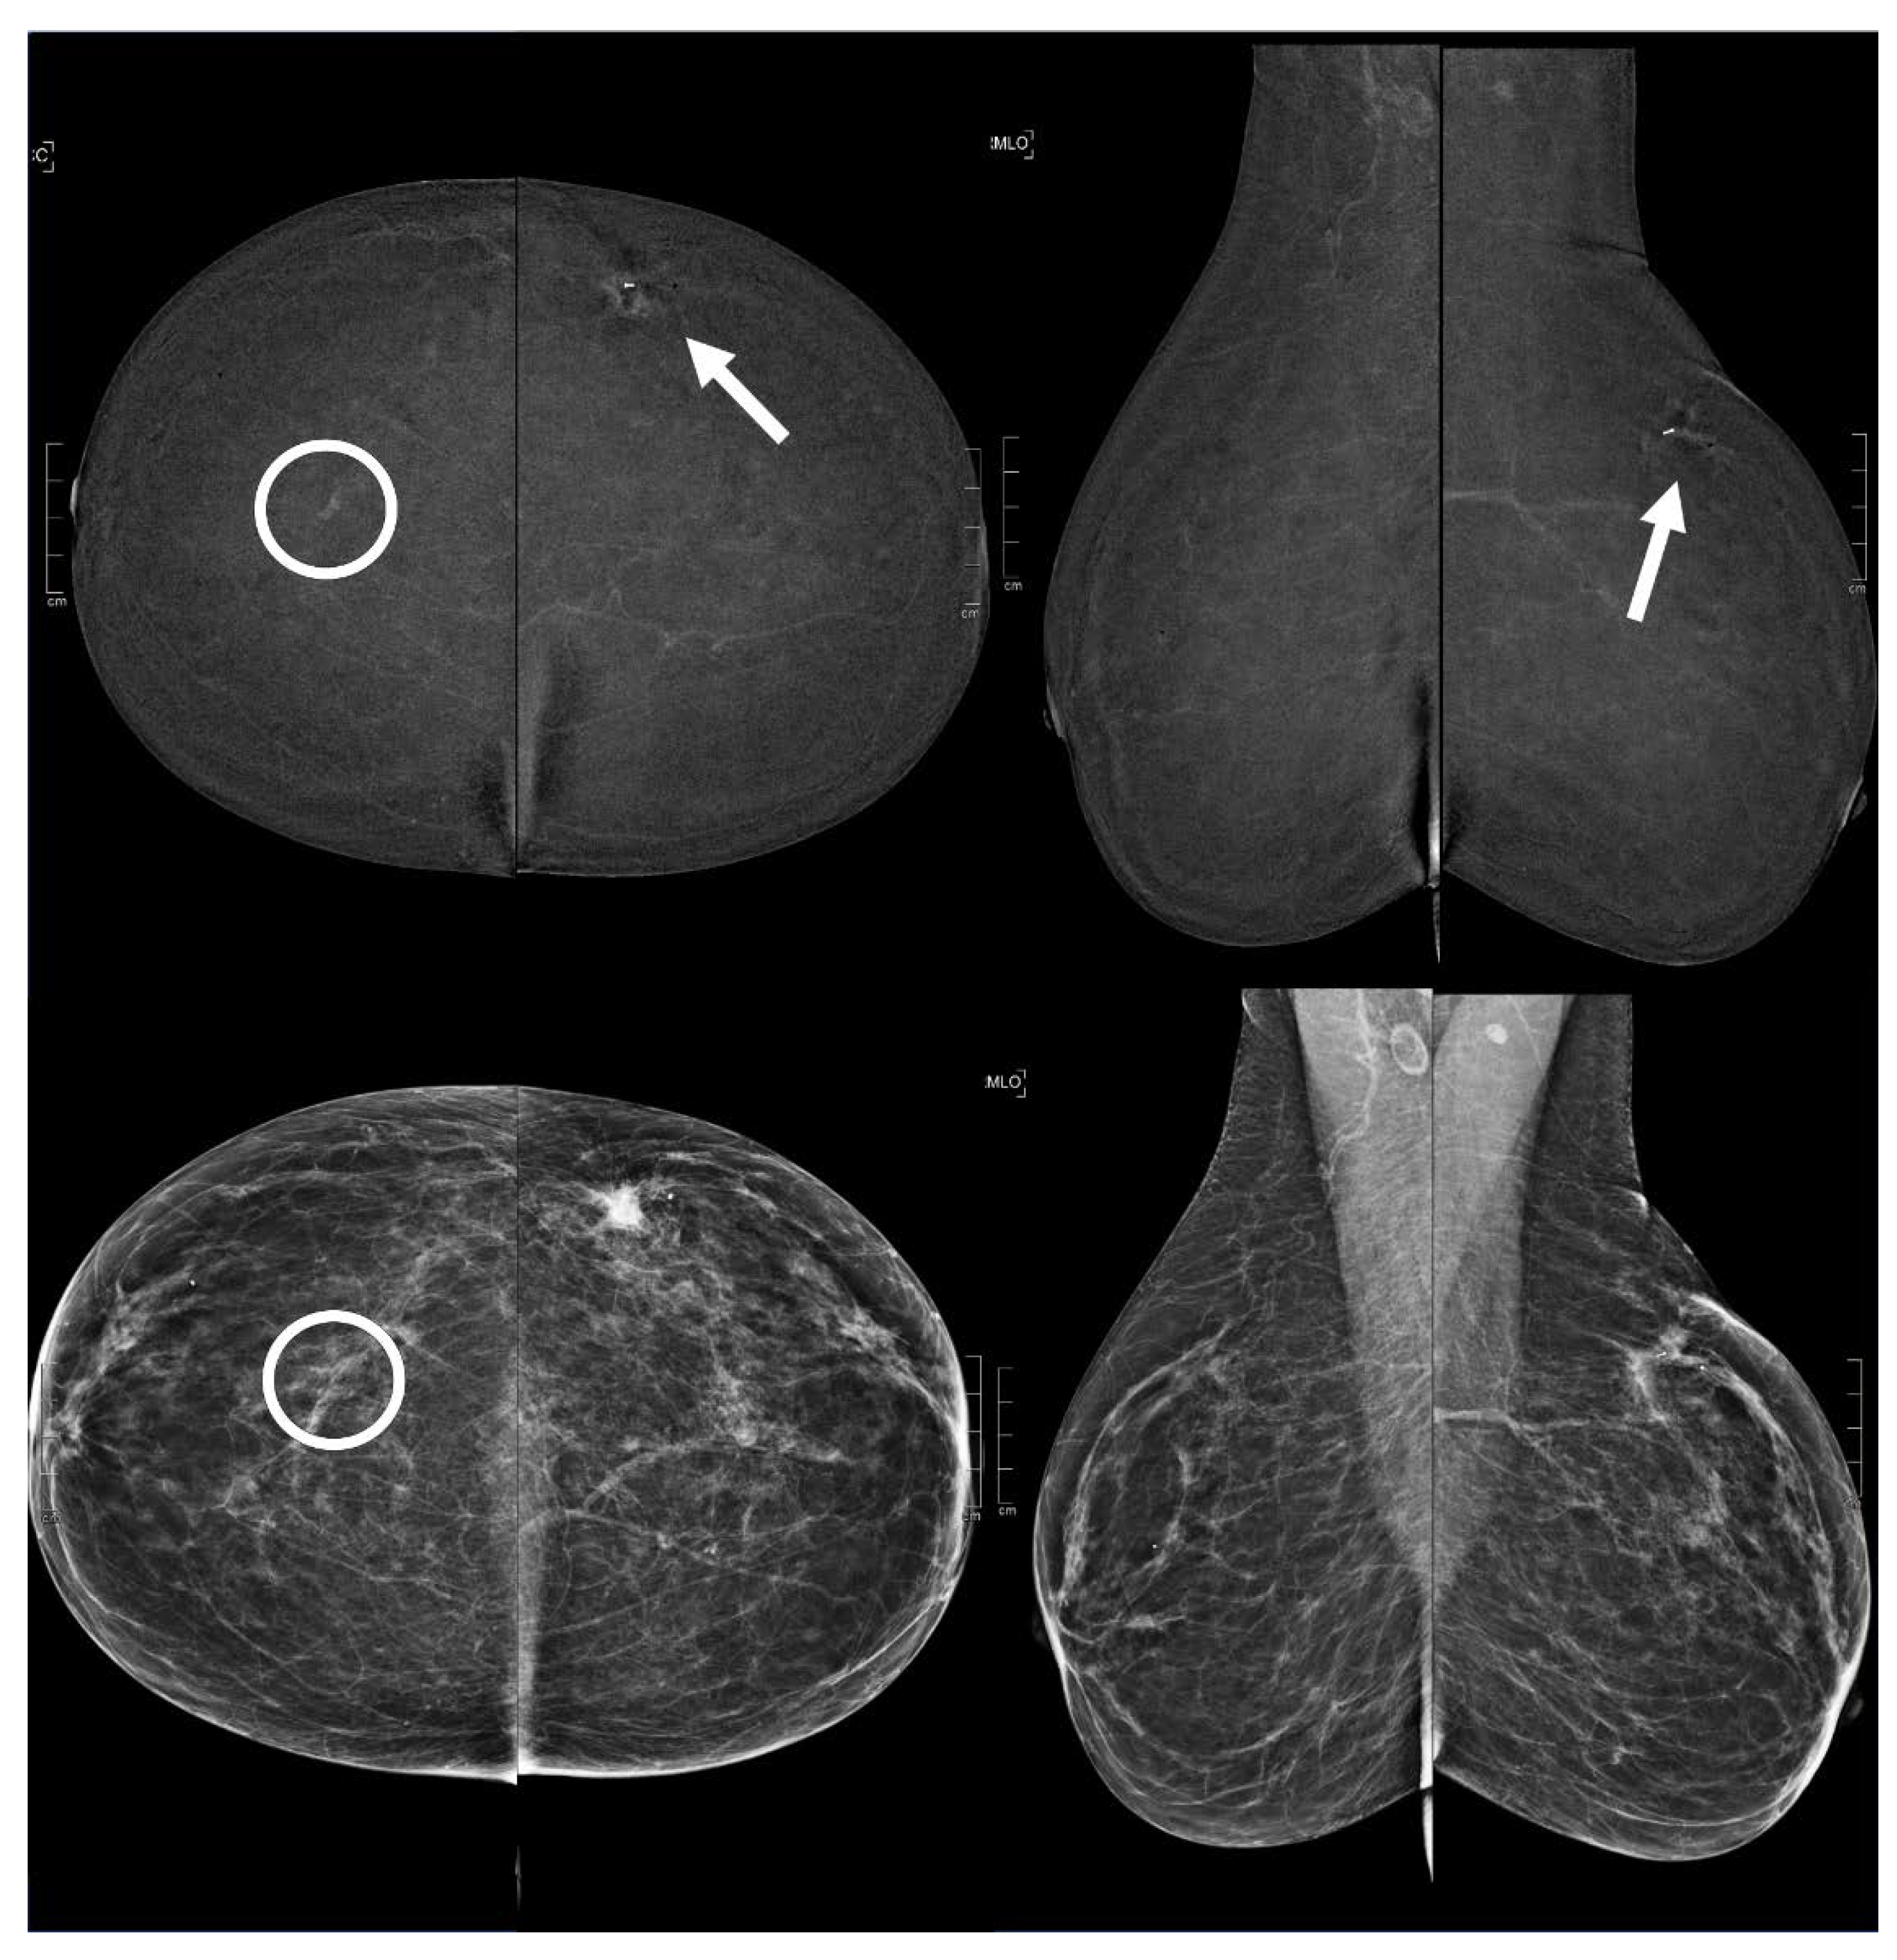

Figure 3.

A 73 year old patient. Contrast-enhanced digital mammography performed as preoperative staging for a B5 lesion in the left breast (arrows). In the early RC in the right breast, there was an enhancing asymmetry in the upper quadrants with high conspicuity only visible in MLO (circle). The EA did not have a clear correspondence in low-energy images. The patient underwent SL-US, which showed a hypoechoic mass of 6.0 mm that was subsequently subjected to CNB (core needle biopsy), which confirmed an invasive tubular carcinoma.